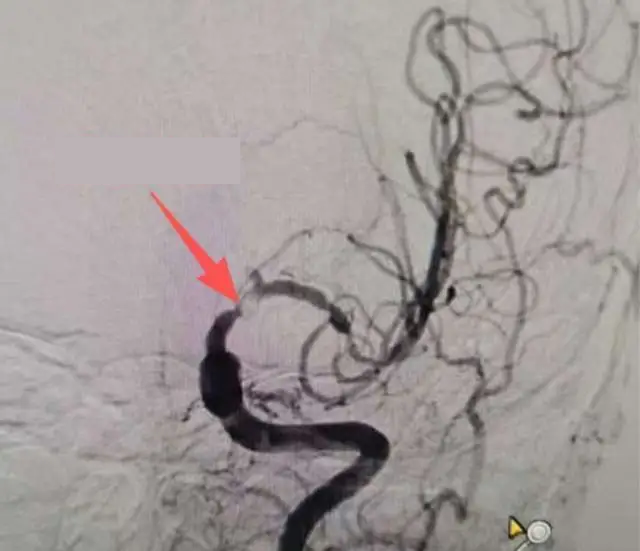

Bác sĩ Chu Nghị, làm việc tại khoa Thần kinh của bệnh viện cho biết, kết quả chụp cộng hưởng từ (MRI) cho thấy trong não ông có ổ nhồi máu mới gây đột quỵ nhồi máu não. Ảnh chụp mạch máu não phát hiện động mạch não trái bị hẹp nghiêm trọng, nếu không điều trị kịp thời có thể dẫn tới liệt nửa người hoặc thậm chí gây tử vong do đột quỵ.

Kết quả chụp mạch máu não của bệnh nhân Ôn. (Ảnh: QQ News)